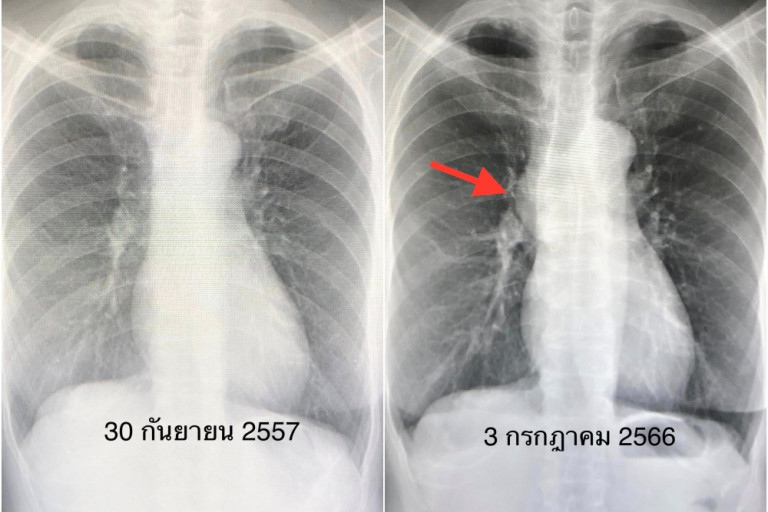

ผู้ป่วยหญิงอายุ 66 ปี ปกติแข็งแรงดี มาตรวจสุขภาพ ทำเอกซเรย์ปอดพบก้อนที่ด้านขวาในช่องกลางของทรวงอก (ดูรูป) ไม่ไอ ไม่เหนื่อย ไม่เบื่ออาหาร น้ำหนักไม่ลด ไม่เจ็บหน้าอก เคยทำเอกซเรย์ปอดครั้งสุดท้ายเมื่อ 9 ปีที่แล้วปกติ (ดูรูป)

ทำคอมพิวเตอร์ปอดพบก้อนอยู่ข้างขวาด้านหน้าตรงกลางทรวงอกขนาด 3.78 × 4.82 × 4.81 เซนติเมตร สงสัยเนื้องอกของต่อมไทมัส (ดูรูป)

ผ่าตัดโดยวิธีส่องกล้อง เมื่อวันที่ 3 กรกฎาคม 2566 ตัดก้อนเนื้อขนาด 5.5 × 4.2 × 2.8 เซนติเมตร ด้านขวาส่วนหน้าของทรวงอกออกได้หมด